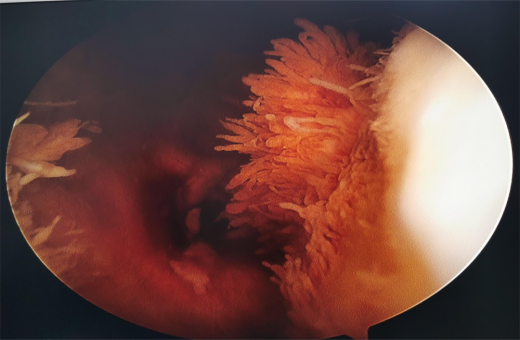

滑膜炎诊断和滑膜切除

4.膝关节炎:如,骨性关节炎、类风湿性关节炎、晶体性滑膜次、化脓性关节类、慢性关节炎。